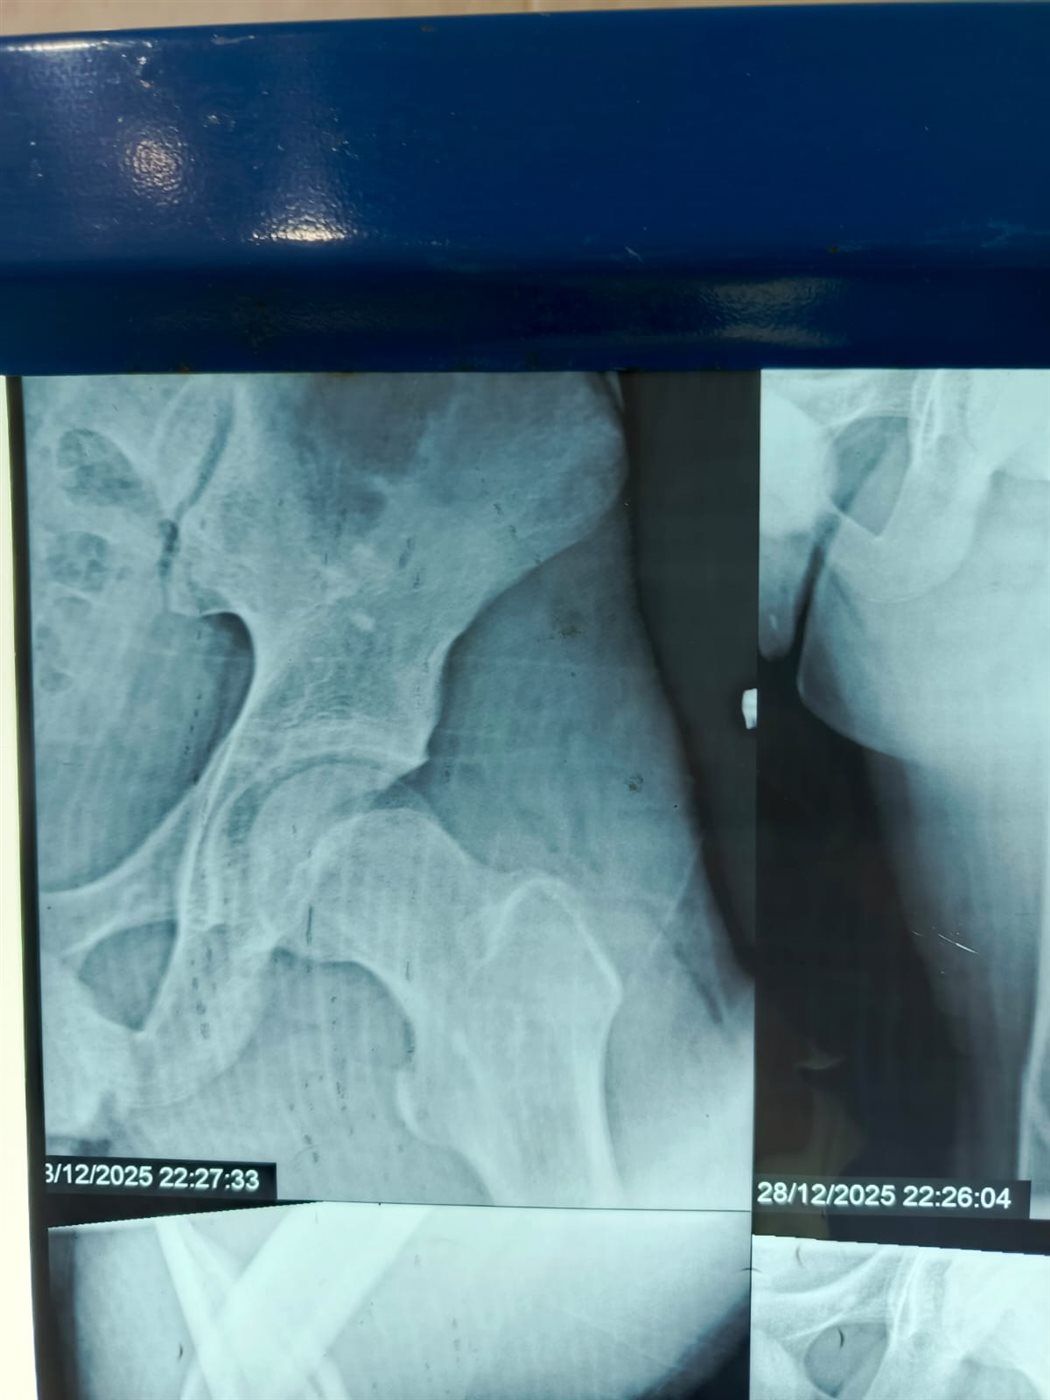

نجح الفريق الطبي بقسم الطوارئ والعمليات بمستشفى مغاغة العام بمحافظة المنيا، في إنقاذ شاب يبلغ من العمر 16 عامًا، تعرض لحادث مروري مروع أسفر عن كسر مفتت متعدد المواضع بعظمة الفخذ الأيسر، وذلك من خلال إجراء جراحة متقدمة باستخدام تقنية المسمار النخاعي التشابكي في زمن قياسي.

وفور وصول المصاب إلى قسم الطوارئ، جرى التعامل الفوري معه، وتم اتخاذ القرار الطبي العاجل بإجراء جراحة المسمار النخاعي التشابكي دون فتح موضع الكسر، بما يتوافق مع أحدث البروتوكولات الطبية العالمية. واستغرقت العملية نحو ساعتين ونصف فقط، غادر بعدها المريض غرفة العمليات في حالة مستقرة.

وتميزت الجراحة بعدة مزايا، من بينها: جروح جراحية محدودة للغاية، وتقليل فرص النزيف والعدوى إلى أدنى حد، وتسريع معدلات التئام العظام مقارنة بالطرق التقليدية.